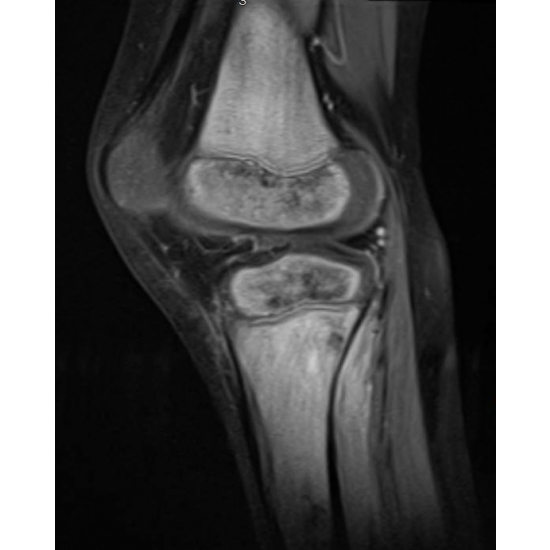

| When A Bike Ride Takes A Wrong Turn - Page #3 | |||